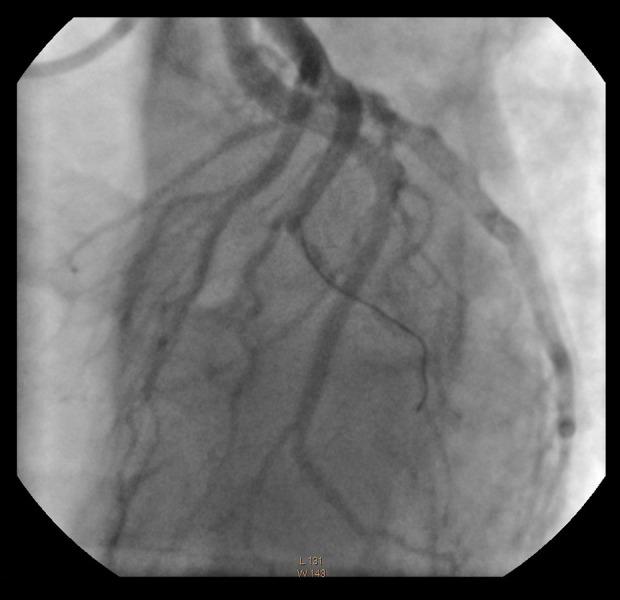

BACKGROUND Acute myocardial infarction during pregnancy is rare, but is associated with a high mortality rate, particularly during labor and delivery. This article concerns a 23-year-old woman with a history of insulin-treated gestational diabetes and hypothyroidism treated with levothyroxine presenting at 32 weeks of pregnancy with acute chest pain and coronary artery occlusion requiring angioplasty followed by cesarean delivery. The aim of this report is to outline the diagnostic difficulties of acute coronary syndromes during pregnancy and to present their treatment. CASE REPORT A 23-year-old female patient at 32 weeks' gestation treated for insulin-dependent diabetes mellitus and hypothyroidism was admitted to the hospital due to acute chest pain. The ECG showed ST-segment elevation in leads I, aVL, and V4-V6 and elevated troponin T. Based on this, the patient was diagnosed with myocardial infarction and given low-molecular heparin, followed by primary coronary angioplasty with revascularization. After the procedure, she received dual antiplatelet therapy (DAPT) with acetylsalicylic acid and clopidogrel. The pregnancy was terminated at 38 weeks by cesarean section, delivering a healthy baby. CONCLUSIONS This report shows the importance of rapid and accurate diagnosis and management of acute myocardial infarction during pregnancy, and delivery by cesarean section, to ensure survival of the mother and the child.

一位 23 岁的女性患者,患有胰岛素依赖型糖尿病和甲状腺功能减退症,在妊娠 32 周时因急性胸痛住院。心电图显示 I、aVL 和 V4-V6 导联的 ST 段抬高和肌钙蛋白 T 升高。基于此,患者被诊断为心肌梗死,并给予低分子肝素,随后进行经皮冠状动脉介入治疗以实现血运重建。手术后,她接受了阿司匹林和氯吡格雷双联抗血小板治疗。在 38 周时通过剖宫产终止妊娠,分娩出一个健康的婴儿。